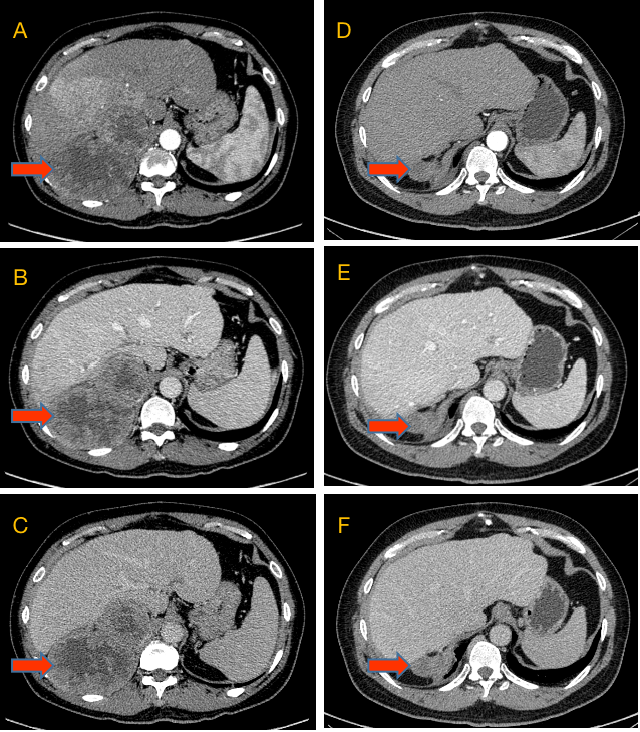

肝癌:增强ct,典型"快进快出".

【临床医生了解】"肝细胞癌"典型ct强化方式,"快进快出"

肝细胞肝癌ct病例图片影像诊断分析

一位典型肝癌ct图像,增强ct鉴别肝癌,肝囊肿肝血管瘤结果要点